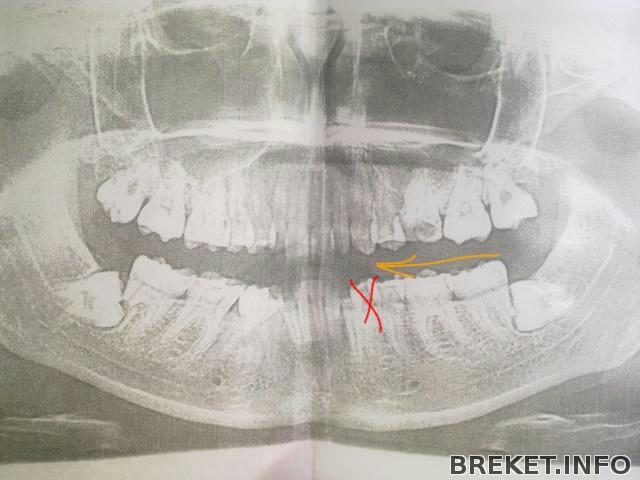

Предложила врачу "оттащить" семерку от восьмерки, такой путь спасения придумал один из хирургов. Правой семерки на НЧ я лишилась из-за того, что корни семерки протаранила ретенированная восьмерка, они рассосались. Восьмерку удалили, одноногая семерка не поняла, как так она осталась без опоры, да еще и со вскрытыми нервами снизу, решила воспалиться и пошла навылет. Теперь же мы попробуем разъединить семерку и восьмерку с левой стороны, надеюсь, что между ними сформируется костная ткань и поврежденный корень семерки останется в стерильных условиях во время и после удаления восьмерки. Это хоть какой-то шанс спасти мне зуб. Вот так вот должны двигаться семерка, шестерка и пятерка на место удаленной четверки

Ортодонт сказала, что подобное передвижение займёт много времени, я ответила, что никуда не тороплюсь.